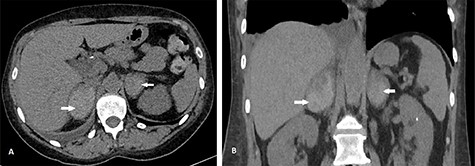

She had sequential CT and ultrasound scans to monitor her adrenal hemorrhages. Adrenal artery embolization was considered in the event of a rebleed and the patient was pre-emptively counseled accordingly. Her hematomas however remained stable on her scans. She had serial hemoglobin monitoring and did not require blood transfusion. She had a heparin-induced thrombocytopenia (HIT) screen on Day 8 on admission and this was negative. She was therefore, managed conservatively and discharged after 11 days. At discharge, she was placed on a reducing dose of oral hydrocortisone to reach target maintenance doses of 10 mg in the morning, 5 mg at noontime and 5 mg at bedtime. She was discharged on fondaparinux and her warfarin was restarted after 5 days when her platelet counts normalized. She had a repeat CT scan 6 weeks post discharge, which showed slow resolution of her hematomas with no underlying mass (Fig. 2).

CT scan after 6 weeks showing axial (A) and coronal (B) views of resolving BAH (arrows). The right adrenal hemorrhage now measures 30 × 46 mm axially and the left adrenal hemorrhage measures 33 × 28 mm.